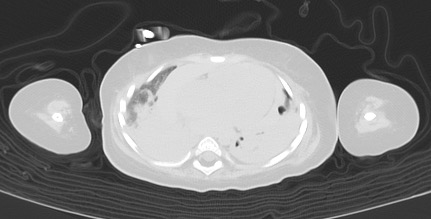

• 肺は特に背側肺で含気を失ない、CT 値で 40~50 程度と比較的高吸収な含気消失となっている。重力分布にしたがって dependent portion の含気低下が対称性に認められ、基本的には長期臥床に伴う荷重部無気肺や沈下肺炎を見ているのではないかと思われるが、一 部は救急蘇生術に伴う肺水腫や血液就下の併存を疑う。

• 気切状態。肺全体としては体全体に対する体積が小さいが、気管・気管支内腔は大きい。 生前に自発呼吸がなく、換気不全が持続していたため、陽圧呼吸下で気道の内腔を大きく拡げる管理がされていたことに合致する。

• 左胸腔の前方には嚢胞状に変化した肺と限局性気管支拡張があり、少量の気胸があるようにも見える。barotrauma、biotrauma 等による 肺の嚢胞性変化が存在していたのではないかと思われ、また空気漏出が起こっていたことが推測される。 生前に単純 X 線写真などでその様な状態あったかどうかは確認が取れるものと思われる。 嚢胞性肺病変などが存在したとしても同様の像が成立しうるので、その可能性を一応指摘しておく。

• 右肺は認められるが、左肺の含気部分には、肺組織が無く、ブラを形成している部分が認められる。CCAM などの先天性空洞性病変や誤嚥による肺の破壊があった可能性がある。 生前に気づかれていないのであれば、後者であろう。